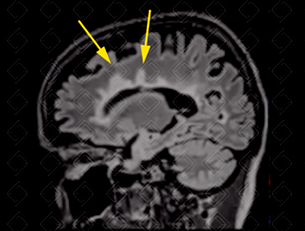

Descrição das imagens: Ressonância magnética de crânio, sequência FLAIR, evidenciando na primeira imagem lesões hiperintensas nos lobos temporais (seta vermelha). Na segunda imagem observamos os clássicos dedos de Dawson, lesões hiperintensas, perpendiculares aos ventrículos laterais (setas amarelas).

• Lesões periventriculares envolvendo os ventrículos laterais, terceiro e quarto ventrículos (mais clássico). Quando as lesões são ovoides e perpendiculares aos ventrículos são chamadas de lesões em dedos de Dawson;